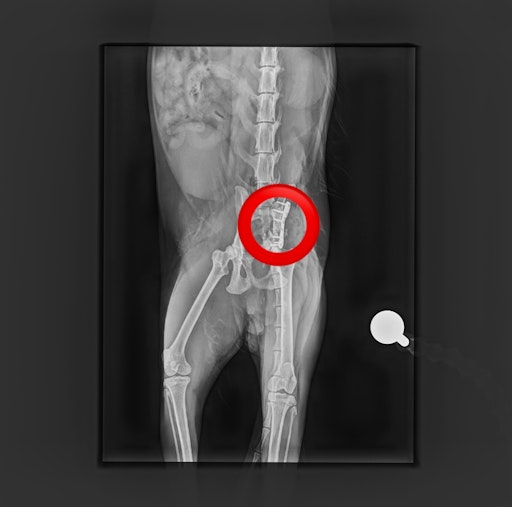

Kürzlich hat der Tierschutzhof Pfotenhilfe einen schwer verletzten Kater aufgenommen, der in Mondsee (OÖ) gefunden wurde und ihn unverzüglich zum auf orthopädische Chirurgie spezialisierten Tierarzt Mag. Daniel Eschlböck in Alkoven (OÖ) gebracht. Dieser hat auf den Röntgenbildern multiple Beckenbrüche festgestellt und bereits eine Seite operiert, jetzt folgt die zweite Operation. Die Verletzungen deuten auf einen Autounfall oder Sturz hin. Der Kater ist natürlich stationär bei ihm untergebracht.